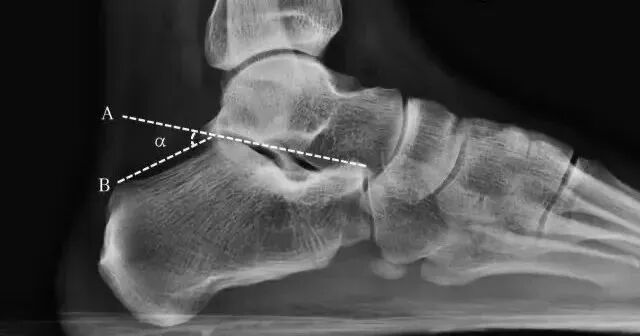

跟骨角

• 正常值:男性28°~40°,女性25°~42°;

• 距跟后关节上缘和跟骨结节后上缘的连线与跟骨上关节面连线间的夹角;

• 跟骨角变小,提示有扁平足或跟骨骨折;角度增大,提示弓形足。